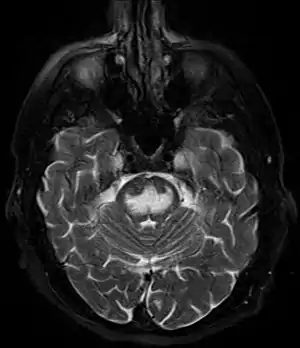

It can be diagnosed clinically in the appropriate context, but may be difficult to confirm radiologically using conventional imaging techniques. Changes are more prominent on MRI than on CT, but often take days or weeks after acute symptom onset to develop. Imaging by MRI typically demonstrates areas of hyperintensity on T2-weighted images.[27]

Central Pontine Myelinolysis -a & b) axial T2W and FLAIR images at the level of pons show central pontine hyperintensity